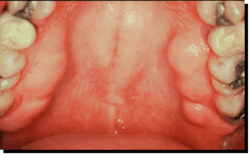

Contrarily, compression of alveolar bone results in additional bone (figures 5 and 6).

Articles on bony protrusions appeared in the literature as early as 1814.12 The negative ions generated from the compression of apatite crystals are believed to be responsible for the aggregates of new bone growth.2